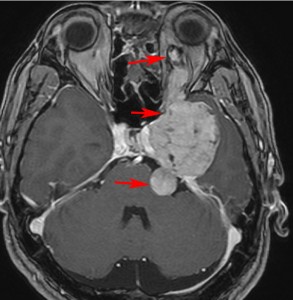

ちょっと大きめの三叉神経鞘腫

メッケル腔(ガッセル神経節)という場所から発生した三叉神経鞘腫のMRIです。サイズは放射線治療するには大きすぎます。ですから手術摘出します。手術には側頭開頭硬膜外法と経鼻内視鏡手術があります。内視鏡手術は三叉神経が外側に来ているので優位性があります。開頭手術では,側頭部の前の方を小さく開頭して脳の硬膜の外から腫瘍を見るだけで取れます。もちろん脳の損傷は起こさないようにしなければなりません。手術中には三叉神経が薄く広がって腫瘍のまわりにくっついていますからそれを大事に守りながら腫瘍を取っていきます。

手術のすぐ後のMRIです。幸いなことにこの患者さんでは,腫瘍を全部取ったのですが三叉神経の大部分を残すことができて,顔のしびれはとても軽くてすみました。全摘出すると経鼻手術でも開頭手術でも多少の顔面の痺れ(感覚低下)はでますが,日常生活に支障のないレベルに留めなければなりません。